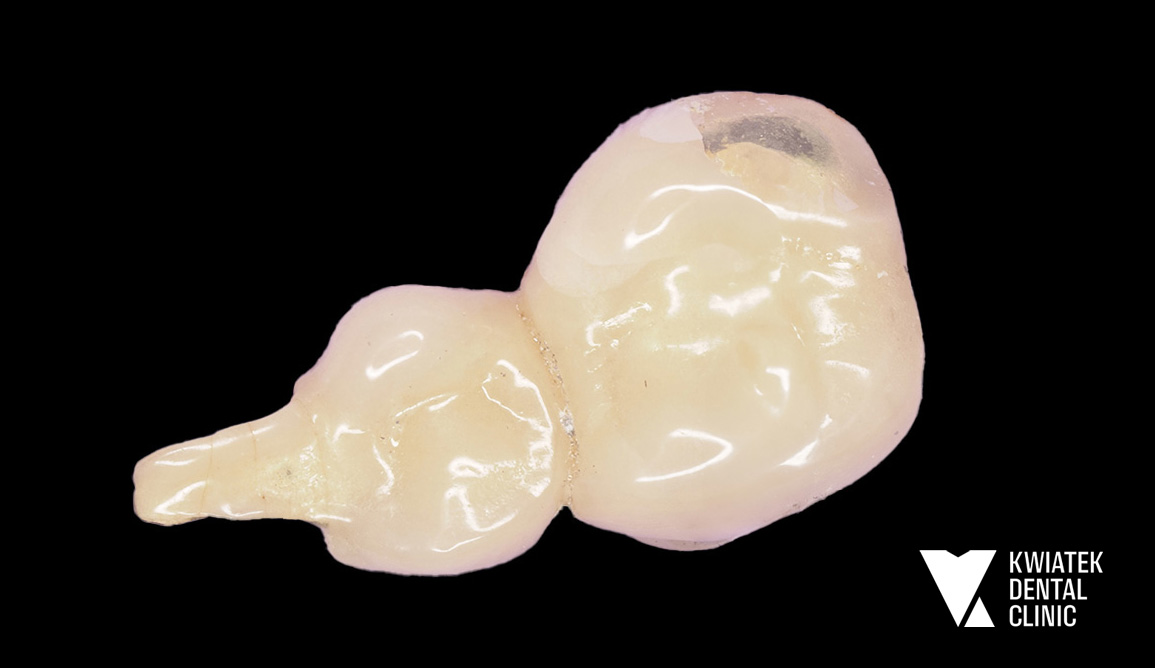

Implant zamiast kompromisu - funkcja i estetyka na najwyższym poziomie

Pacjentka przez lata użytkowała starą pracę protetyczną w odcinku 16 do 14, która z czasem przestała spełniać zarówno funkcję estetyczną, jak i funkcjonalną. Po szczegółowej diagnostyce zaproponowano najnowocześniejsze i najbardziej przewidywalne rozwiązanie w postaci implantacji w miejscu brakującego zęba 15 oraz wykonanie nowych koron ceramicznych. Efektem jest trwała, komfortowa i naturalnie wyglądająca odbudowa, przywracająca prawidłowe warunki żucia i harmonię uśmiechu.